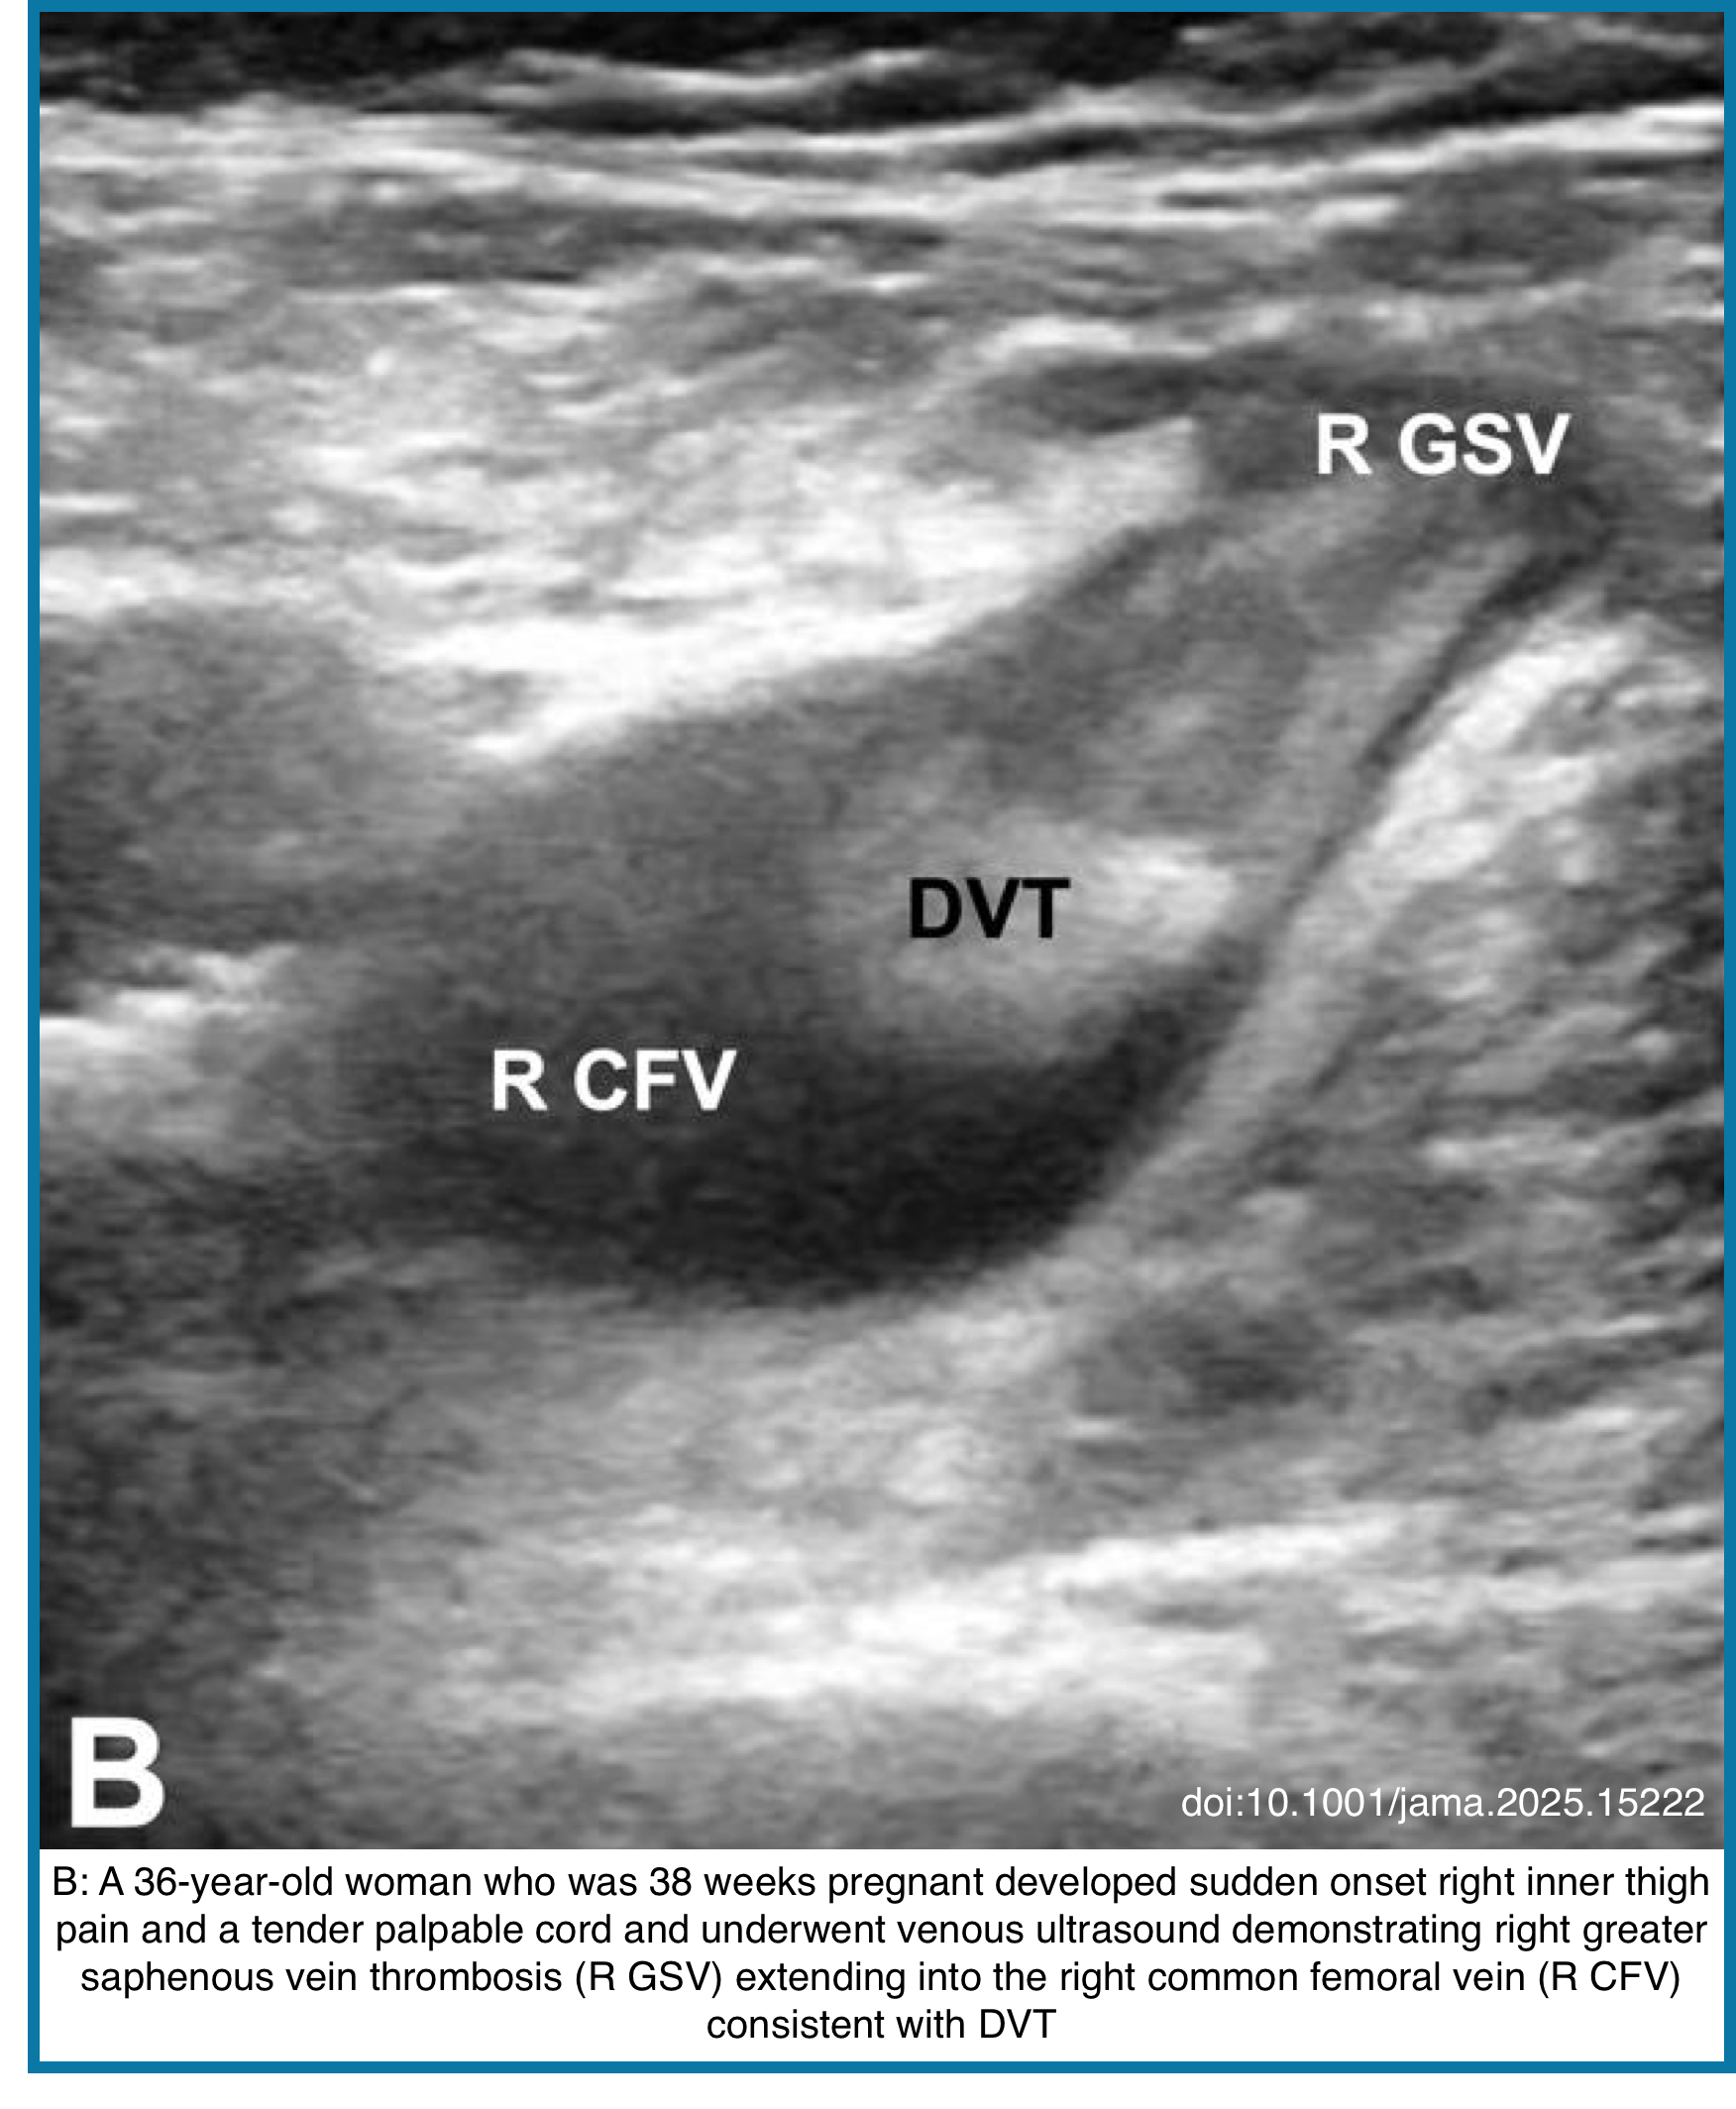

Pregnancy

◾️Epidemiology & Risk

- Pregnancy increases VTE risk 4-5×; the postpartum period carries the highest risk

- 90% of pregnancy DVTs occur in the left leg due to anatomical compression (May-Thurner physiology)

- Risk peaks in the 3rd trimester and the first 6 weeks postpartum

◾️Clinical Presentation

- Symptoms overlap with normal pregnancy: leg swelling, pain, warmth

- 🚩Red flags: Unilateral leg swelling (especially left), calf pain, swelling above the knee

◾️Diagnosis

- Compression ultrasound (CUS) is first-line

- Whole-leg ultrasound preferred over proximal-only

- Perform in the left lateral decubitus position in late pregnancy

- D-dimer use is limited: Levels rise normally in pregnancy; cutoff unclear

- Clinical prediction rule: “LEFt” mnemonic → Left leg, Edema (≥2 cm difference), First trimester presentation (see below).

- If ultrasound negative but suspicion high → consider Doppler of iliac veins or MR venography